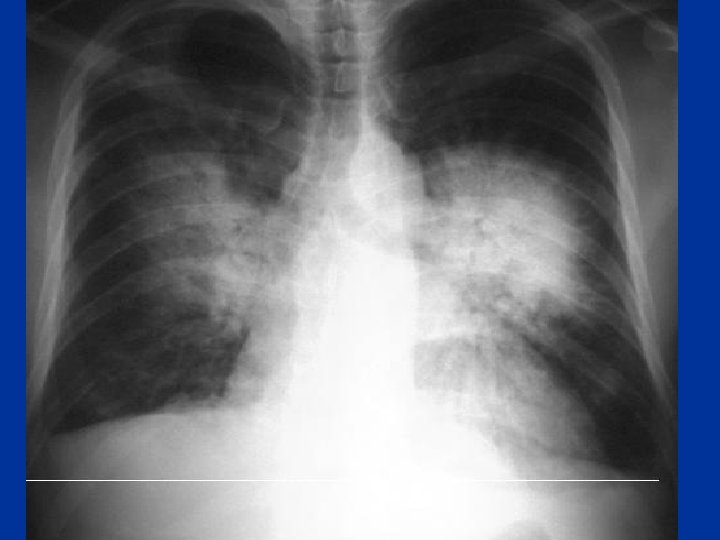

Pulmonary Edema Risk factors: • Smoking • HTN-DM, lipid • Gallop rhythm • ECG, CE • Murmur • Chest x-ray or prior H/O • heart cocaine • LL use • Edema • H/O rheumatic heart disease Symptoms: • Orthopnea, PND’s • Assoc. chest pain • Palpitations • Sweating JVP • Bibasilar crackles